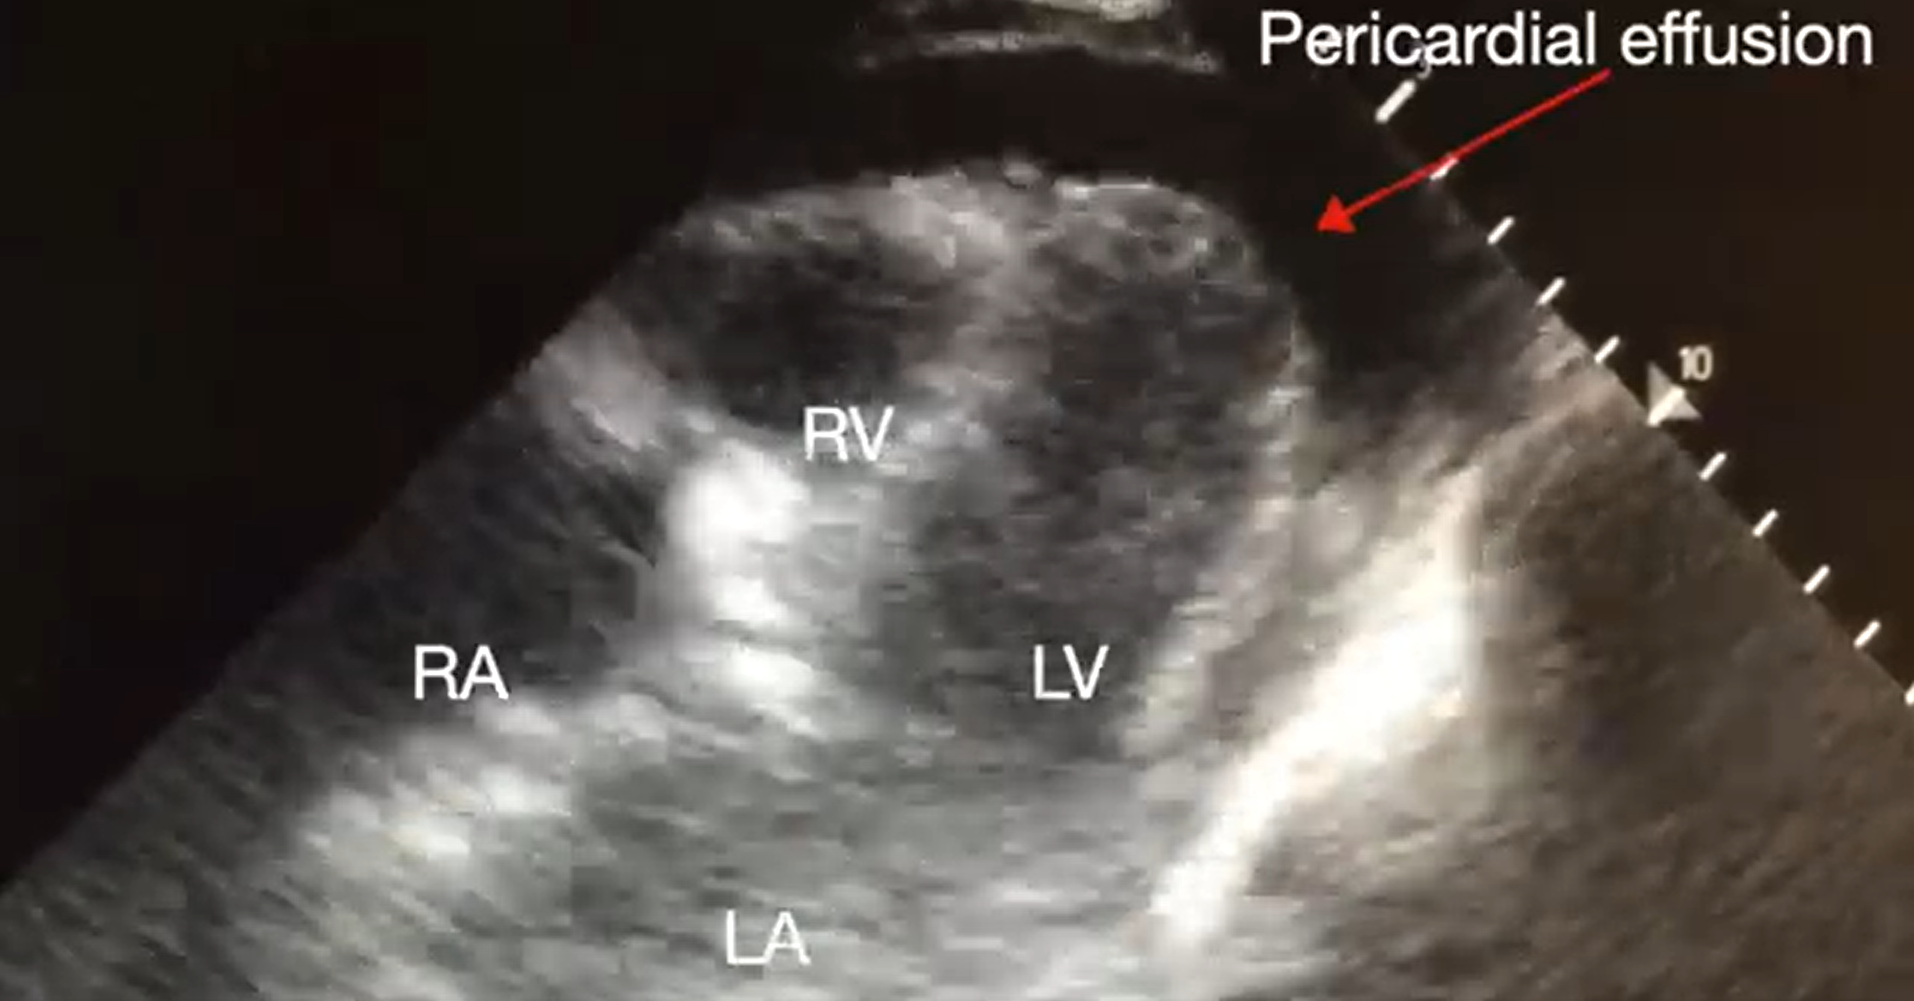

Pericardial tamponade is identified in 5%-22% of patient with PEA arrest.6,7 POCUS findings of pericardial tamponade include the presence of either small (acutely developing) or large (chronically developing) pericardial effusion, right atrial (RA) systolic collapse, right ventricular (RV) diastolic collapse, and plethoric inferior vena cava (IVC) (Videos 2 and 3). The diagnosis of tamponade using POCUS may be difficult in post-cardiac surgery patients who frequently present with a localized collection; transesophageal echocardiography (TEE) should then be used to make the diagnosis. A concomitant pleural effusion might potentially worsen the tamponade physiology. Therefore, imaging of the pleural space can be performed during chest compressions, with thoracentesis possibly reversing the tamponade physiology8 (Video 4).

Video 2. Subcostal 4-chaber view demonstrating pericardial effusion. RA, right atrium; LA, left atrium; RV, right ventricle; LV, left ventricle (click to view)

Supplemental Video 3. Subcostal IVC view demonstrating plethoric inferior vena cava (IVC) during chest compressions. RA, right atrium. (click to view)